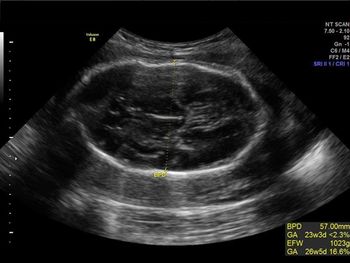

Challenge your diagnostic skills with this image of a fetal head.